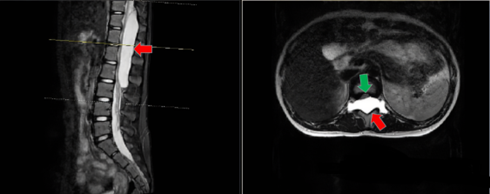

劉女士一直有流涕的毛病,周圍的親戚朋友都說是鼻炎,平時(shí)工作繁忙,她也沒有在意,但這幾年連續(xù)發(fā)生幾次腦膜炎,一次還送到了ICU進(jìn)行搶救,要不是治療及時(shí)差點(diǎn)丟了性命。最近劉女士的鼻涕越來越多,而且有些特別的是她只有一側(cè)鼻子流,鼻涕很清亮,像純凈水一樣,她到底是什么病呢?在當(dāng)?shù)蒯t(yī)院一直也沒有診斷清楚。后經(jīng)人介紹劉女士慕名來到北京大學(xué)人民醫(yī)院耳鼻咽喉頭頸外科找到王旻醫(yī)生就診,當(dāng)被告知得的是“腦脊液鼻漏”,不及時(shí)治療非常危險(xiǎn)時(shí),可把劉女士嚇了一跳,后來經(jīng)過王旻醫(yī)生內(nèi)鏡下微創(chuàng)手術(shù)治療,劉女士的“腦脊液鼻漏”被治好了,此后再也沒有出現(xiàn)腦膜炎的情況。每個(gè)人都可能會(huì)流鼻涕,大部分情況并不嚴(yán)重,但如果鼻涕是一側(cè)的清水樣涕,就可能是腦脊液鼻流,腦脊液鼻漏到底是一個(gè)什么樣的疾病呢?又如何診斷治療呢?下面我們一起來了解一下這個(gè)疾?。呵辶恋囊后w從單側(cè)鼻腔流出正常人的腦組織和顱骨之間有清亮的液體稱為腦脊液,腦脊液是由腦室脈絡(luò)叢產(chǎn)生,主要成分包括無機(jī)鹽、葡萄糖、微量蛋白,成人每天腦脊液約120ml,起到緩沖壓力、調(diào)節(jié)顱壓、保護(hù)營(yíng)養(yǎng)腦組織的作用。當(dāng)顱底的骨質(zhì)、硬腦膜、蛛網(wǎng)膜破損,腦脊液就可以流入鼻腔及鼻咽部,稱為“腦脊液鼻漏”。腦脊液鼻漏的病因和分類:腦脊液鼻漏主要分四種:·外傷性:車禍、外傷損傷顱底引起·自發(fā)性:由于某些原因?qū)е嘛B內(nèi)壓力增高、鼻竇過度氣化、病變破壞等因素,出現(xiàn)腦脊液鼻漏·醫(yī)源性:在鼻竇手術(shù)時(shí)損傷顱底,出現(xiàn)腦脊液鼻漏·腦脊液鼻漏伴腦膜腦膨出,有些患者先天顱底缺損,腦膜、腦組織可以從顱底疝入道鼻竇,膨出的腦組織多為無功能性的。病因:包括肥胖、高顱壓、睡眠呼吸暫停低通氣綜合征、鼻竇過度氣化等因素,均可誘發(fā)此病。臨床表現(xiàn):·鼻腔間斷或持續(xù)流出清亮、水樣液體,多為單側(cè);·低頭用力、壓迫頸靜脈時(shí)液體流出量增加(Furstenbergtest)。·外傷性的CSF可見血性液體,中央紅色,周邊清澈,不結(jié)痂;·反復(fù)腦膜炎;·咳嗽,吸入性肺炎;診斷:定性診斷·病史·腦脊液常規(guī)及生化檢查,腦脊液葡萄糖含量在1.7mmol/L以上;·β-2轉(zhuǎn)鐵蛋白檢測(cè)、β-2示蹤蛋白檢測(cè)等,一般醫(yī)院沒有此類方法;定位診斷·鼻內(nèi)鏡;·高分辨CT:顱底骨質(zhì)缺損、病變部位軟組織影;·MRI,水成像;·腦池造影;·熒光素鞘內(nèi)注射;(IntrathecalFluoresceinInjection)鑒別診斷:變應(yīng)性鼻炎、血管運(yùn)動(dòng)性鼻炎等;鼻竇黏膜下囊腫;伴有哮喘的鼻鼻竇炎;治療:保守治療包括·臥床頭抬高30度;·潤(rùn)腸通便、避免用力增加顱壓、腹壓的動(dòng)作;·避免打噴嚏、擤鼻涕、咳嗽、憋氣;·藥物治療:抗生素預(yù)防感染,乙酰唑胺、甘露醇降低顱壓等;手術(shù)治療:保守治療無效則需要及時(shí)進(jìn)行手術(shù)治療,防止出現(xiàn)顱內(nèi)感染危及生命。目前主流的手術(shù)方式是內(nèi)鏡下進(jìn)行腦脊液鼻漏修補(bǔ)手術(shù),手術(shù)的關(guān)鍵是找到漏口,根據(jù)漏口的大小、位置,選擇合適的手術(shù)入路進(jìn)行修補(bǔ)。常用的修補(bǔ)材料包括:自體材料如游離或者帶蒂的鼻腔粘膜、鼻中隔軟骨和骨質(zhì)、大腿闊筋膜、脂肪肌肉,異體材料如:人工硬膜、脫細(xì)胞真皮、止血紗布等。內(nèi)鏡手術(shù)的優(yōu)點(diǎn)很多:創(chuàng)傷小、恢復(fù)快、手術(shù)視野清晰、準(zhǔn)確判斷漏點(diǎn)、方便選取鼻腔黏膜軟骨進(jìn)行修補(bǔ)等,但對(duì)醫(yī)生的手術(shù)技術(shù)要求高,有些特殊部位的漏點(diǎn)如:額竇、蝶竇外側(cè)隱窩的暴露困難,對(duì)術(shù)者技術(shù)要求更高。如果內(nèi)鏡治療無效可以聯(lián)合外進(jìn)路聯(lián)合治療。預(yù)后腦脊液鼻漏一般預(yù)后良好,但如果合并顱壓增高,則需要請(qǐng)神經(jīng)內(nèi)外科會(huì)診降低顱壓,否則即使手術(shù)很成功,還有再次復(fù)發(fā)的可能。紅色箭頭所指的就是額竇后壁巨大顱底缺損的一例腦積液鼻漏、腦膜腦膨出的患者,這位患者有腦部腫瘤病史,經(jīng)過前期多次外路手術(shù)失敗,經(jīng)內(nèi)鏡下修補(bǔ)后成功解決問題;